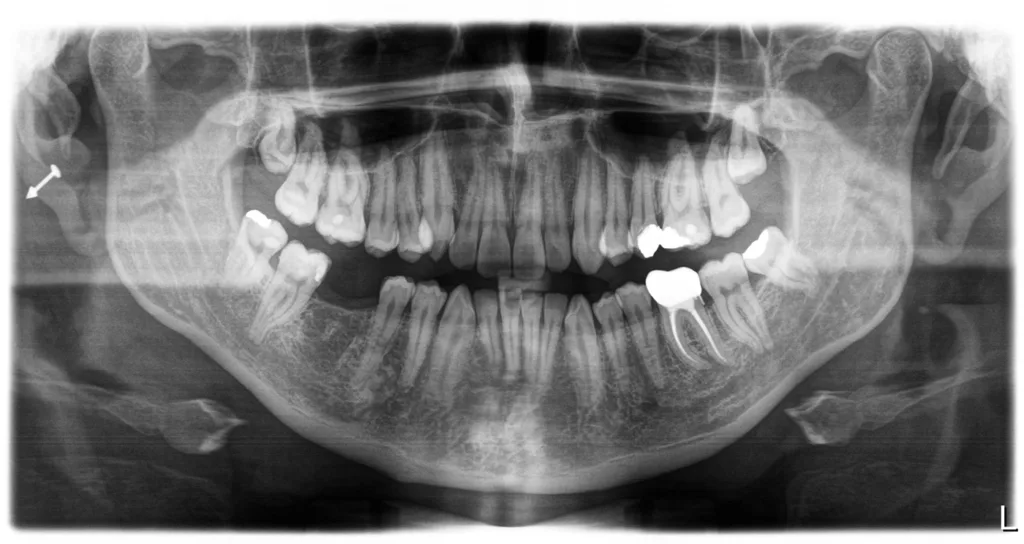

![Abb. 3a: Klinische Dokumentation einer 24-jährigen Patientin mit einer weit fortgeschrittenen lokalen parodontalen Destruktion, die mit großer Wahrscheinlichkeit durch ein Zungenpiercing hervorgerufen wurde [10]. Mit Ausnahme der Symptomatik im Unterkiefer-Frontzahnbereich wies die Patientin flache Sondierungstiefen und einzelne Regionen mit Gingivitis auf. Die Zähne reagierten positiv auf eine Sensibilitätsprobe mit Kältespray. Das Piercing war zum Zeitpunkt der Vorstellung in der Klinik bereits nicht mehr im Mund. Es wurde eine stufenweise systematische parodontale Therapie eingeleitet. Die verbliebenen und nahezu unveränderten erhöhten Son¬dierungstiefen wurden einem parodontal-chirurgischen Eingriff mit zusätzlichen, die Regenera¬tion fördernden Maßnahmen (Straumann Emdogain, Straumann, Basel, Schweiz) unterzogen. Es wurde die für diese Operationen empfohlene Schnittführung im Sinne eines Papillenerhaltungs¬lappens angewendet. Der nach der Degranulierung mit Hand- und Ultraschallinstrumenten sicht¬bare knöcherne Defekt wies eine ungünstige Morphologie für die Regeneration auf. Ein primärer Wundverschluss wurde dennoch erzielt. Diese Ansätze blieben letztendlich erfolglos und der Zahn 41 ging verloren (parodontologische Therapie gemeinsam mit Dr. L. Büttel, Basel, Schweiz).](https://dentalwelt.spitta.de/wp-content/uploads/2025/07/Abb-3a-1024x684.webp)

![Abb. 3b: Klinische Dokumentation einer 24-jährigen Patientin mit einer weit fortgeschrittenen lokalen parodontalen Destruktion, die mit großer Wahrscheinlichkeit durch ein Zungenpiercing hervorgerufen wurde [10]. Mit Ausnahme der Symptomatik im Unterkiefer-Frontzahnbereich wies die Patientin flache Sondierungstiefen und einzelne Regionen mit Gingivitis auf. Die Zähne reagierten positiv auf eine Sensibilitätsprobe mit Kältespray. Das Piercing war zum Zeitpunkt der Vorstellung in der Klinik bereits nicht mehr im Mund. Es wurde eine stufenweise systematische parodontale Therapie eingeleitet. Die verbliebenen und nahezu unveränderten erhöhten Son¬dierungstiefen wurden einem parodontal-chirurgischen Eingriff mit zusätzlichen, die Regenera¬tion fördernden Maßnahmen (Straumann Emdogain, Straumann, Basel, Schweiz) unterzogen. Es wurde die für diese Operationen empfohlene Schnittführung im Sinne eines Papillenerhaltungs¬lappens angewendet. Der nach der Degranulierung mit Hand- und Ultraschallinstrumenten sicht¬bare knöcherne Defekt wies eine ungünstige Morphologie für die Regeneration auf. Ein primärer Wundverschluss wurde dennoch erzielt. Diese Ansätze blieben letztendlich erfolglos und der Zahn 41 ging verloren (parodontologische Therapie gemeinsam mit Dr. L. Büttel, Basel, Schweiz).](https://dentalwelt.spitta.de/wp-content/uploads/2025/07/Abb-3b-1024x684.webp)

![Abb. 3c: Klinische Dokumentation einer 24-jährigen Patientin mit einer weit fortgeschrittenen lokalen parodontalen Destruktion, die mit großer Wahrscheinlichkeit durch ein Zungenpiercing hervorgerufen wurde [10]. Mit Ausnahme der Symptomatik im Unterkiefer-Frontzahnbereich wies die Patientin flache Sondierungstiefen und einzelne Regionen mit Gingivitis auf. Die Zähne reagierten positiv auf eine Sensibilitätsprobe mit Kältespray. Das Piercing war zum Zeitpunkt der Vorstellung in der Klinik bereits nicht mehr im Mund. Es wurde eine stufenweise systematische parodontale Therapie eingeleitet. Die verbliebenen und nahezu unveränderten erhöhten Son¬dierungstiefen wurden einem parodontal-chirurgischen Eingriff mit zusätzlichen, die Regenera¬tion fördernden Maßnahmen (Straumann Emdogain, Straumann, Basel, Schweiz) unterzogen. Es wurde die für diese Operationen empfohlene Schnittführung im Sinne eines Papillenerhaltungs¬lappens angewendet. Der nach der Degranulierung mit Hand- und Ultraschallinstrumenten sicht¬bare knöcherne Defekt wies eine ungünstige Morphologie für die Regeneration auf. Ein primärer Wundverschluss wurde dennoch erzielt. Diese Ansätze blieben letztendlich erfolglos und der Zahn 41 ging verloren (parodontologische Therapie gemeinsam mit Dr. L. Büttel, Basel, Schweiz).](https://dentalwelt.spitta.de/wp-content/uploads/2025/07/Abb-3c-1024x722.webp)

![Abb. 3d: Klinische Dokumentation einer 24-jährigen Patientin mit einer weit fortgeschrittenen lokalen parodontalen Destruktion, die mit großer Wahrscheinlichkeit durch ein Zungenpiercing hervorgerufen wurde [10]. Mit Ausnahme der Symptomatik im Unterkiefer-Frontzahnbereich wies die Patientin flache Sondierungstiefen und einzelne Regionen mit Gingivitis auf. Die Zähne reagierten positiv auf eine Sensibilitätsprobe mit Kältespray. Das Piercing war zum Zeitpunkt der Vorstellung in der Klinik bereits nicht mehr im Mund. Es wurde eine stufenweise systematische parodontale Therapie eingeleitet. Die verbliebenen und nahezu unveränderten erhöhten Son¬dierungstiefen wurden einem parodontal-chirurgischen Eingriff mit zusätzlichen, die Regenera¬tion fördernden Maßnahmen (Straumann Emdogain, Straumann, Basel, Schweiz) unterzogen. Es wurde die für diese Operationen empfohlene Schnittführung im Sinne eines Papillenerhaltungs¬lappens angewendet. Der nach der Degranulierung mit Hand- und Ultraschallinstrumenten sicht¬bare knöcherne Defekt wies eine ungünstige Morphologie für die Regeneration auf. Ein primärer Wundverschluss wurde dennoch erzielt. Diese Ansätze blieben letztendlich erfolglos und der Zahn 41 ging verloren (parodontologische Therapie gemeinsam mit Dr. L. Büttel, Basel, Schweiz).](https://dentalwelt.spitta.de/wp-content/uploads/2025/07/Abb-3d-1024x665.webp)

Wir sind vor mittlerweile 17 Jahren erstmals mit der Frage etwaiger Auswirkungen oraler Piercings auf den Zahnhalteapparat konfrontiert worden [10]. Eine damals 24-jährige Patientin stellte sich mit einem ungewöhnlichen Befund vor (Abb. 3a bis d). Bei sonst parodontal unauffälligen Verhältnissen mit Sondierungstiefen zwischen 2 und 3 mm, reichten die Sondierungstiefen an den Schneidezähnen im Unterkiefer bis 12 mm. Zahn 41 schmerzte und wies eine erhöhte Lockerung von Grad 2 auf. Bukkal war zudem eine Fistel mit Pusentleerung zu detektieren. Die Patientin war allgemeinmedizinisch gesund, rauchte nicht und hatte auch keinen Diabetes mellitus. Eine familiäre Prädisposition für parodontale Erkrankungen ließ sich anamnestisch nicht konstruieren. Die Mundhygiene war zwar nicht perfekt, stand aber auch in keinem Verhältnis zu ihrem dramatischen lokalen parodontalen Befund. Im Rahmen der anamnestischen Befragung, fokussiert auf ungewöhnliche Habits, berichtete die Patientin, bis vor kurzem ein Zungenpiercing getragen zu haben, dieses aber vor ca. sechs Monaten entfernt zu haben. Die Piercing-Tragedauer betrug etwa drei Jahre.

In der Gesamtschau der zusammengetragenen Daten und unter Berücksichtigung der in medizinischen Datenbanken aufgefundenen einzelnen Fallbeschreibungen erschien uns die wahrscheinlichste Ursache für den vorliegenden Befund tatsächlich das Zungenpiercing zu sein [11]. Die parodontale nicht-chirurgische, wie auch die chirurgisch-regenerative Therapie waren nicht erfolgreich und die Patientin verlor den stark kompromittierten Unterkiefer-Frontzahn. Seit dieser Zeit beschäftigen wir uns intensiver mit diesem Thema. So begannen wir mit der Sammlung und Erfassung der klinischen Parameter bei Patienten/-innen, die ein orales Piercing tragen oder einst trugen. Die Ergebnisse wurden zunächst im Rahmen einer Masterarbeit ausgewertet, als Posterbeitrag bei der Europerio 9 in Amsterdam veröffentlicht und später dann als Manuskript publiziert [10,12].